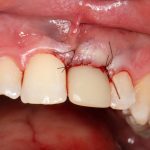

Давайте внимательно посмотрим на состояние лунок центральных резцов после удаления:

Приемлемый фенотип (сочетание толщины и ширины участка жевательной десны) — это, конечно, приятно. Но гораздо важнее сосредоточиться на рисках, их на этот момент два:

— травматическое повреждение слизистой, вызванное удаление зубов связано с тем, что при хроническом воспалении слизистая оболочка теряет эластичность, поэтому легко рвётся. Такая ситуация создаёт серьёзную угрозу эстетическому результату лечения, в зависимости от того, насколько быстро десна придёт в норму.

— как и предполагалось после КЛКТ, утрата костной стенки привела к тому, что десна провалилась в просвет лунки левого центрального резца. Это еще больше усугубляет клиническую ситуацию.

Для нас это не было неожиданностью. Зная закономерности изменений тканей при хроническом  воспалении и данные КЛКТ, мы можем довольно точно предсказывать развитие клинической ситуации и соответственно к ней подготовиться. Именно поэтому, помимо обычной немедленной имплантации, мы запланировали аугментацию лунки с помощью биоматериалов и метода трансплантации лоскута (см. предварительные планы лечения).